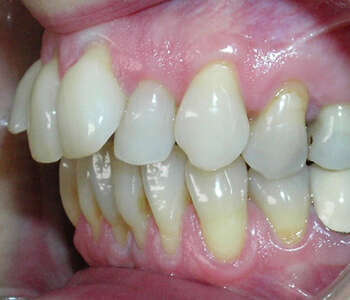

Cas 2 : Incisives trop avancées